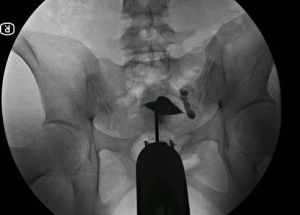

二、子宮輸卵管碘油造影術(HSG)

子宮輸卵管碘油造影術操作簡單,可在螢屏下直視子宮及輸卵管內部結構和形態。其優點是:1、診斷迅速,準確,術中即可判定子宮原因或輸卵管原因,部位確切。有研究表明,HSG判斷梗阻部位優於腹腔鏡。2、可在直視下適當加大壓力,以分離輕度宮腔粘連。3、安全,因在直視下操作,可發現術中意外情況,如碘化油進人血管、淋巴,及時停止注藥,以防油栓發生引起不良後果。但其所用造影劑(如碘油)不良反應大,易刺激黏膜引起過敏,且油性造影劑粘稠,難以通過輸卵管狹窄部,判斷梗塞部位較困難。